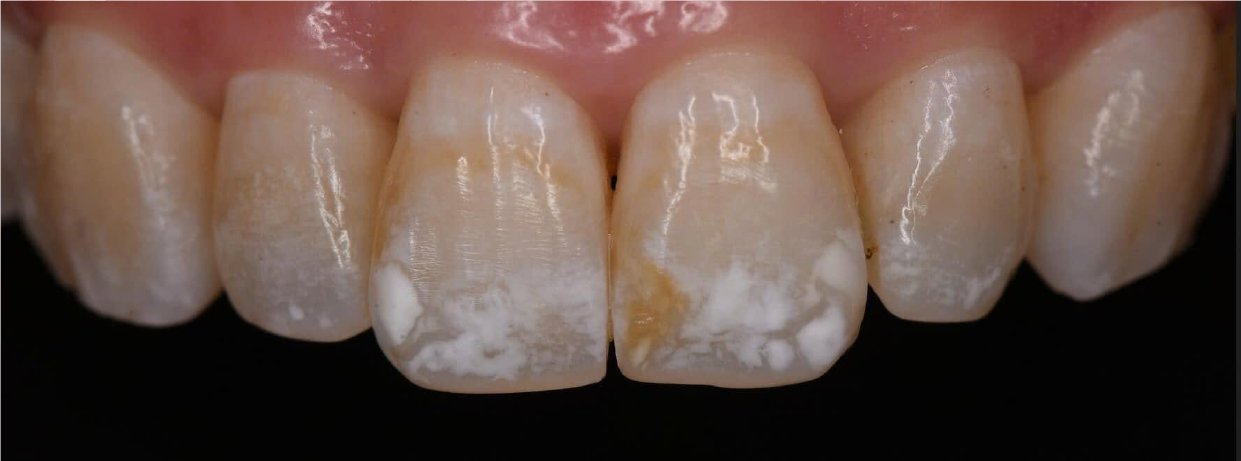

Hình Ảnh Trước & Sau Điều Trị

Minh chứng rõ ràng cho chất lượng và hiệu quả tại Nha khoa Như Ngọc – nơi mỗi khách hàng đều tìm lại được nụ cười tự tin sau quá trình điều trị và thẩm mỹ răng